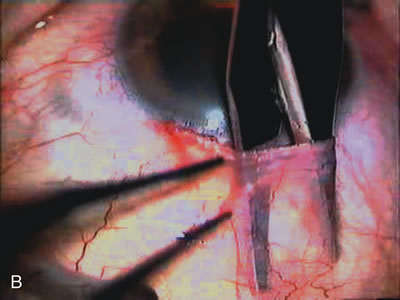

Fig. 1. The anatomic advantage of small incision cataract surgery for the glaucoma patient. A. Long-term bleb function with a large cataract incision is difficult to achieve with either ECCE-trabeculectomy or trabeculectomy followed later by ECCE. This bleb failed to form sufficiently when combined with large incision ECCE. The inflammation, bleeding, and long-term wound healing with stimulation of fibroblasts associated with this technique are more likely to cause bleb failure. In addition, the increased iris manipulation necessary to deliver the nucleus and subsequent iris repair adds to the long-term breakdown of the blood aqueous barrier. B and C. Two-site phacotrabeculectomy has the advantage of small incision cataract surgery combined with separate site trabeculectomy. The incision size is one third the size of the standard ECCE. The inflammation is less severe, and cataract wound healing is confined to the temporal area. Visual rehabilitation with phacoemulsification and foldable IOL is much faster. Phacoemulsification allows successful lens extraction even in the unfriendly environment of a smaller pupil compared with ECCE. The trabeculectomy is performed in an entirely different site, well away from the wound healing associated with temporal phacoemulsification. The likelihood of this filter functioning long-term is greater than with ECCE-trabeculectomy. D. The surgeon also has the option of single-site phacotrabeculectomy with foldable IOL. Both the lens extraction and trabeculectomy are performed through one small 3.5-mm limbal incision.